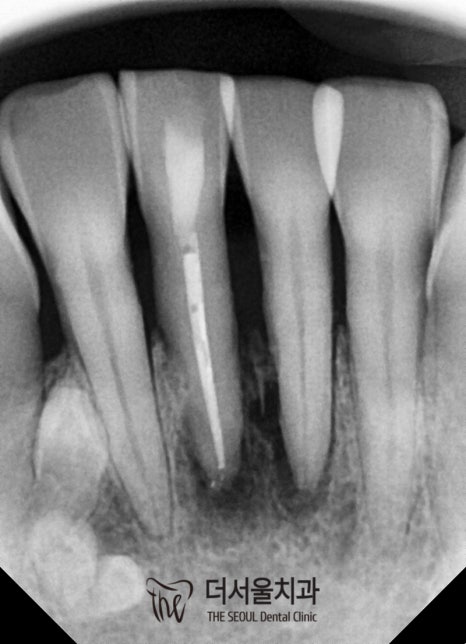

다행히 최종 보철을 올려도 될 정도로

상태가 완화된 것을 확인했는데요.

환자께서도 흔들리고 아픈 게 하나도 없다며

임시로 올려둔 것도 너무 편하다는 말씀을 해주셨죠.

한 달이 지나고,

치근단염증 을 확인하기 위해

더서울을 다시 내원해 주셨던 환자분!

다행히 병소의 크기도 점점 줄어들어

거의 잡혀가는 것이 관찰되었으며

흔들림이나 통증도 나타나지 않았습니다.